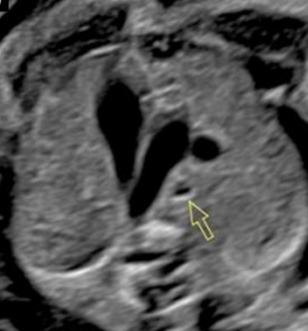

What view is this?

outflow tract